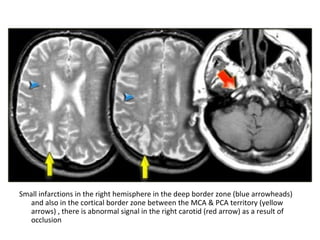

Small infarctions in the right hemisphere in the deep border zone (blue arrowheads)

and also in the cortical border zone between the MCA & PCA territory (yellow

arrows) , there is abnormal signal in the right carotid (red arrow) as a result of

occlusion